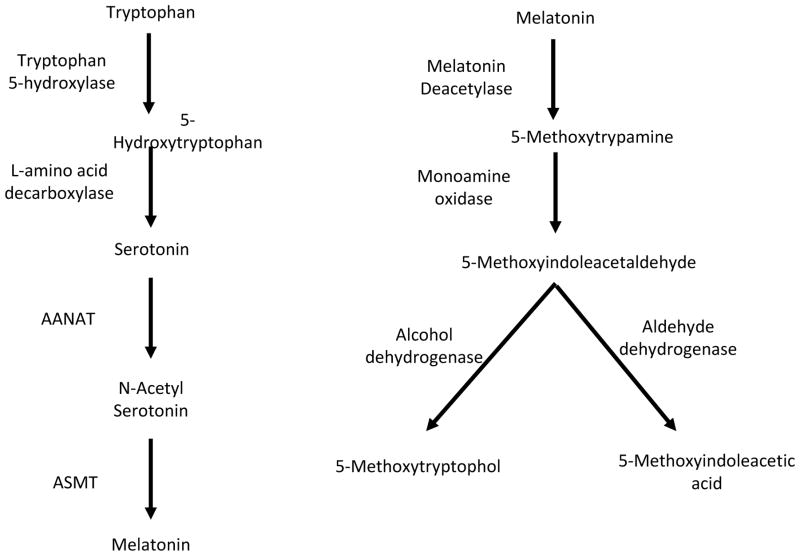

- Melatonin is derived from the amino acid tyrptophan. R

- Tryptophan is converted to serotonin by AANAT (arylalkylamine N-acetyltransferase), which converts serotonin to N-acetylserotonin. R

- ASMT (Acetylserotonin O-methyltransferase) is an ezyme that is encoded by the ASMT gene and that catalyzes the final reaction in melatonin biosynthesis, converting Normelatonin to melatonin. R